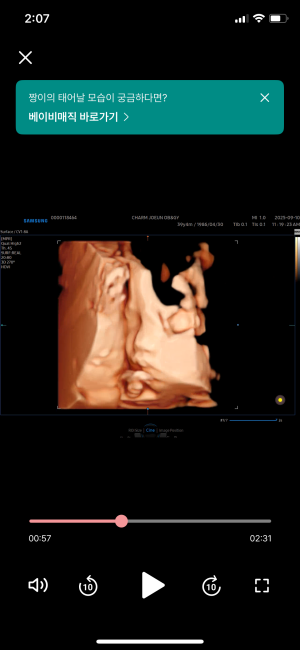

드디어 32주 ! 9개월!

박포포

2025-10-02